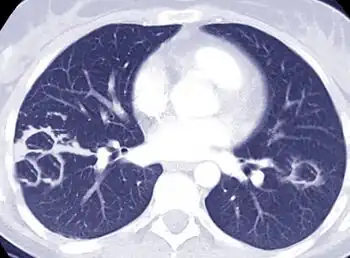

Pulmonary disease caused by NTM is most often seen in postmenopausal women and patients with underlying lung disease such as cystic fibrosis, bronchiectasis, and prior tuberculosis. It is not uncommon for alpha 1-antitrypsin deficiency, Marfan syndrome, and primary ciliary dyskinesia patients to have pulmonary NTM colonization and/or infection. Pulmonary NTM can also be found in individuals with AIDS and malignant disease. It can be caused by many NTM species, which depends on region, but most frequently MAC and M. kansasii.[11]

Clinical symptoms vary in scope and intensity, but commonly include chronic cough, often with purulent sputum. Hemoptysis may also be present. Systemic symptoms include malaise, fatigue, and weight loss in advanced disease.[12] The diagnosis of M. abscessus pulmonary infection requires the presence of symptoms, radiologic abnormalities, and microbiologic cultures.

Pulmonary NTM disease diagnosis requires both identification of the mycobacterium in the patient's lung(s), as well as a high-resolution CT scan of the lungs.